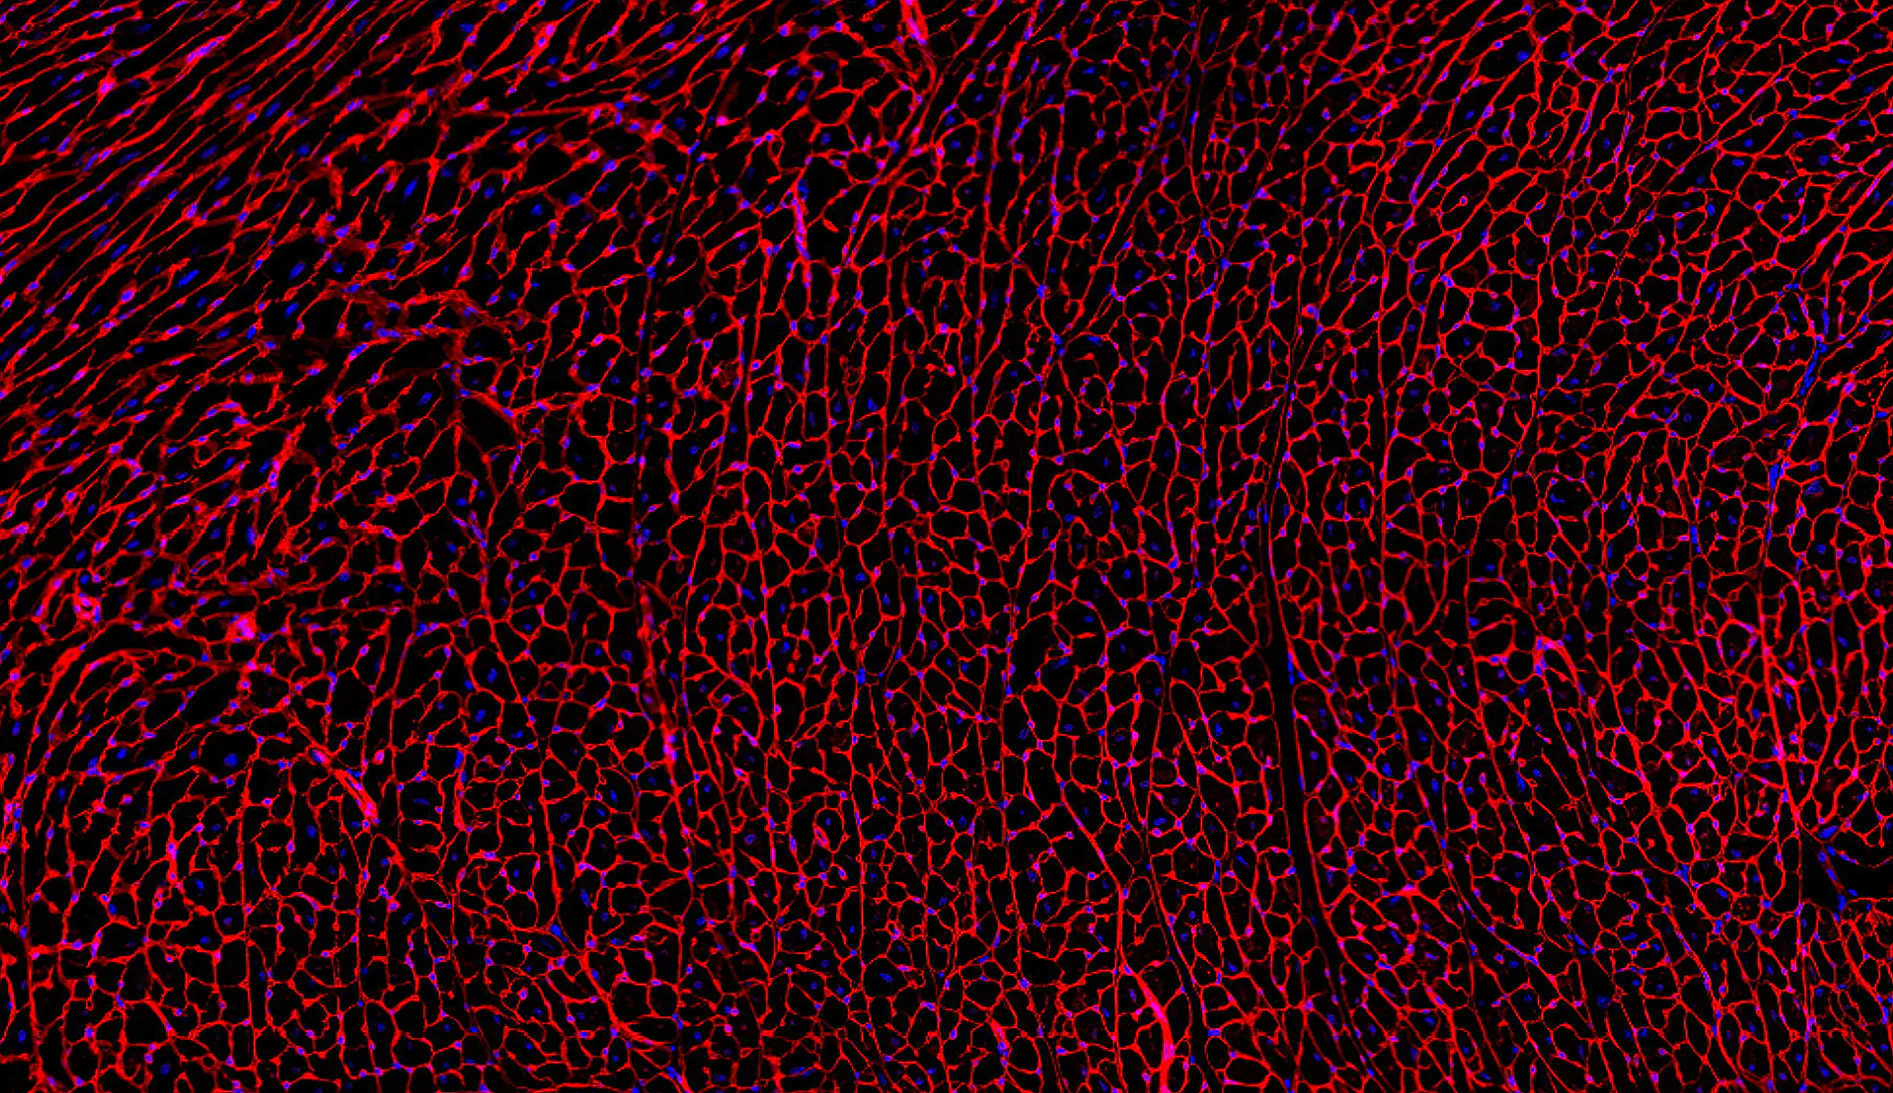

Extracellular matrix–immune crosstalk

Our work elucidates how matrix components such as hyaluronan act as dynamic signaling platforms that regulate inflammation, fibrosis, and ventricular adaptation.